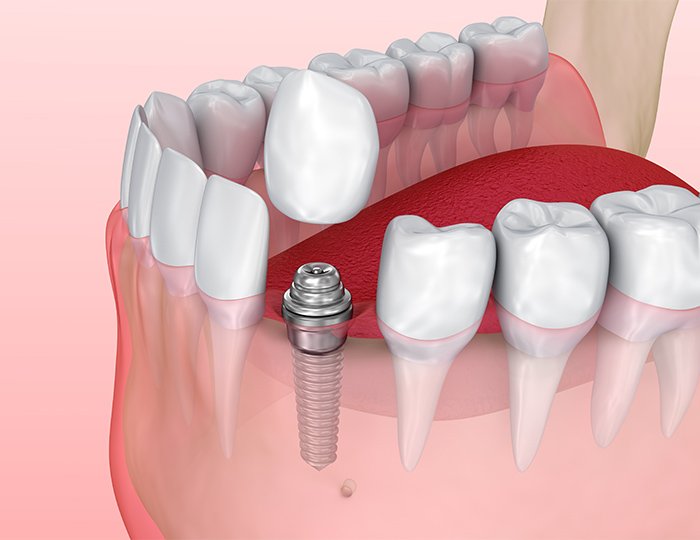

インプラント治療は、永久歯を喪失してしまった場合に行う治療法のひとつです。この治療では歯を失った部分に、金属製(人体に悪影響のないチタンまたはチタン合金)のインプラント体を埋め込み、その上に人工歯を装着する治療です。入れ歯やブリッジでは、しっかりと噛めない、残っている天然歯への負担が気になるといった場合に、検討したい治療法です。

インプラント治療は、顎の骨の歯槽骨をドリリングした穴に、チタンやチタン合金でできた生体親和性が高い金属製の人工歯根(インプラント体)を埋め込む外科手術を行います。この埋入されたインプラント体が、歯槽骨にしっかりと結合するまで待機する期間があるため、治療期間は3種類の治療法の中で最も期間を要します。

インプラント治療は、顎の骨の歯槽骨をドリリングした穴に、チタンやチタン合金でできた生体親和性が高い金属製の人工歯根(インプラント体)を埋め込む外科手術を行います。この埋入されたインプラント体が、歯槽骨にしっかりと結合するまで待機する期間があるため、治療期間は3種類の治療法の中で最も期間を要します。

しかし、顎の骨にしっかり固着したインプラント体に人工歯の土台となるアバットメントを固定しますので、外れてしまう心配がほとんどありません。本来の自分の歯のような感覚で食事や会話が行えます。天然歯と変わらず歯磨きが可能です。